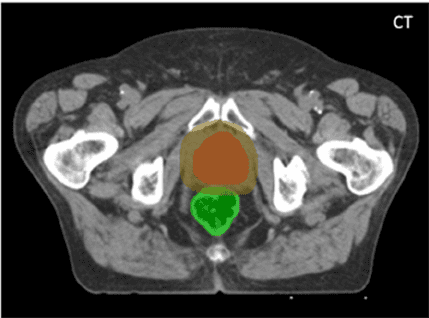

Что покажет КТ предстательной железы

Компьютерная томография простаты проводится для определения состояния железы, мочевого пузыря, семенных пузырьков и прямой кишки с анусом. Список основных показаний к проведению компьютерной томографии предстательной железы включает: воспаление в исследуемой области, появлением лимфаденита у пациентов; подозрения на рак простаты; нанесение ударов и травм и огневых ранений в область промежности и живо